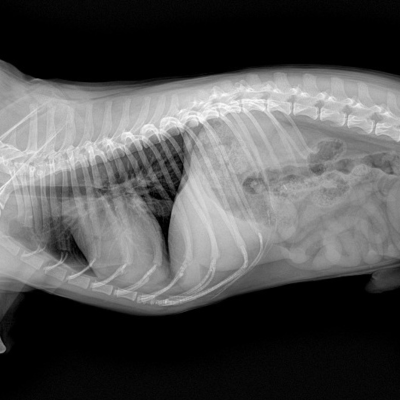

Evcil hayvanların sağlığını korumanın en etkili yollarından biri düzenli kan tahlilleridir. Kamacı Veteriner Kliniği, gelişmiş laboratuvar imkanlarıyla biyokimya ve hemogram testleri sayesinde hastalıkların erken teşhisini sağlar ve tedavi sürecini hızlandırır.

Hemogram, evcil hayvanların genel sağlık durumunu değerlendirmek için yapılan kapsamlı bir kan testidir.

Biyokimya testleri, organların çalışma durumunu değerlendirmek için yapılır. Özellikle karaciğer, böbrek ve pankreas fonksiyonları hakkında önemli bilgiler verir.

Evcil hayvanlar, hastalık belirtilerini çoğu zaman geç gösterir. Bu nedenle düzenli olarak yapılan kan testleri, görünmeyen sağlık sorunlarının ortaya çıkarılmasında kritik rol oynar.

Kamacı Veteriner Kliniği'nde yapılan biyokimya ve hemogram testleri, modern cihazlar ile kısa sürede sonuçlandırılır. Bu sayede doğru teşhis hızlıca konularak tedaviye zaman kaybetmeden başlanır.

Sonuçların Uzman Değerlendirilmesi